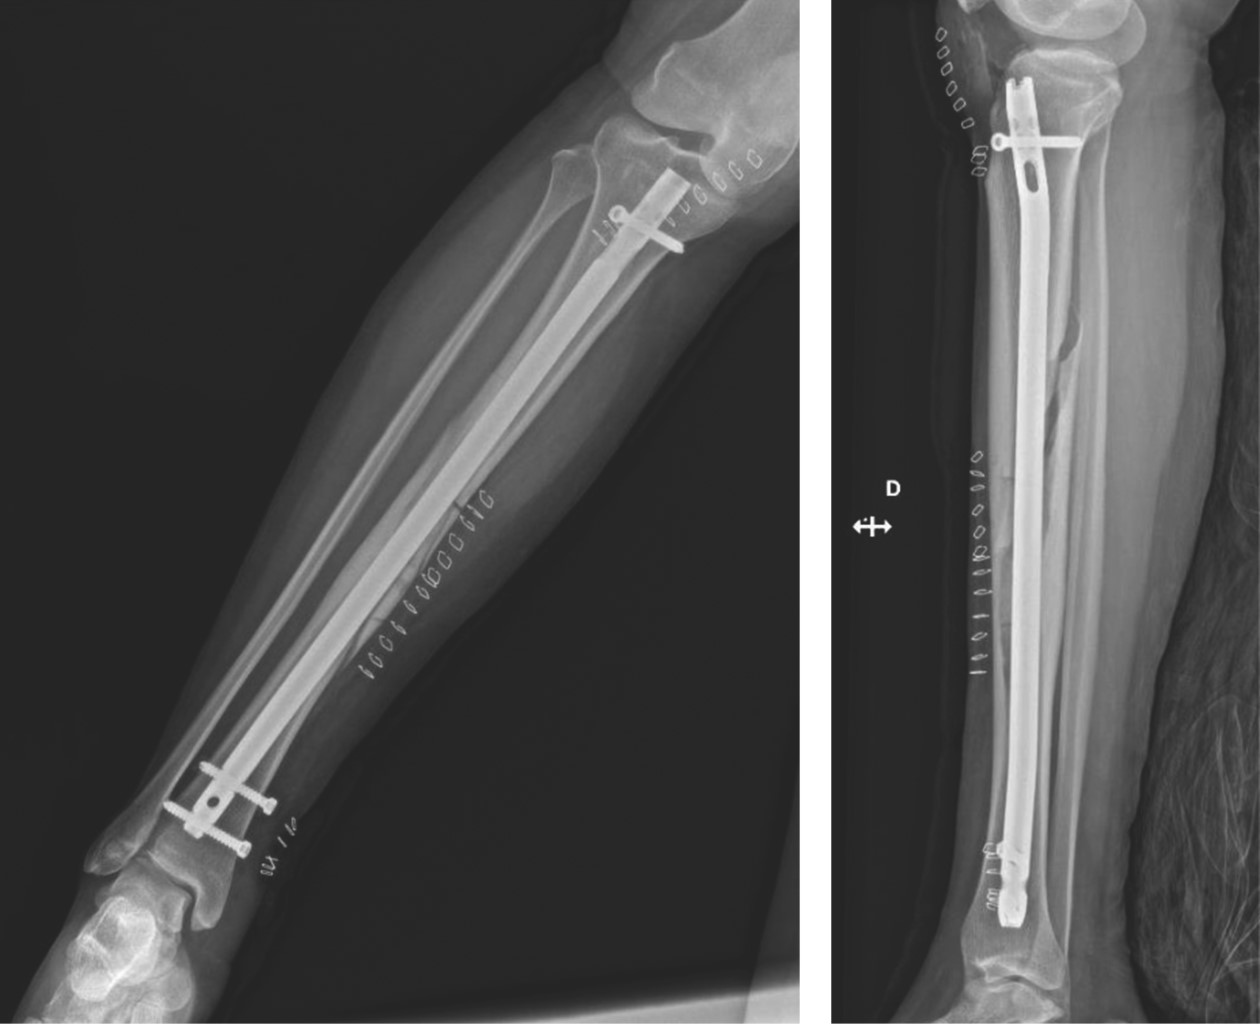

Ante la persistencia de los síntomas, a pesar del tratamiento analgésico y los resultados no concluyentes de las pruebas de imagen y laboratorio, se realizó un exhaustivo diagnóstico diferencial y se llegó al diagnóstico de enfermedad de Ribbing. Se optó por un tratamiento quirúrgico mediante enclavado intramedular (Figura 3).

PROCEDIMIENTO Y EVOLUCIóN

Se realizó enclavado endomedular de tibia, con imposibilidad de progresión del fresado a través de la lesión. Se realizó una ventana ósea anterior y limpieza de foco lesional. Durante el procedimiento, se produjo una fractura espiroidea proximal de tibia, que quedó bien reducida tras la osteosíntesis.

Figura 3